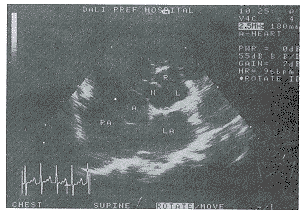

中国超声医学杂志991224 患者男,21岁,因心悸,气促,胸骨旁第三、四肋之间闻及Ⅳ级双期杂音并向胸前广泛传导,可触及震颤,颈静脉怒张,而行心脏彩超检查。示:左房、左室、右房、右室增大,以右房、右室为明显,在主动脉根部短轴切面见无冠窦呈花瓣状向右房内突出(图1),瘤体壁薄,底部大,内口1.45cm,顶部小外口0.65cm,瘤体长径达4.65cm。彩色多普勒示破口处及其附近见蓝色为主五色相间的双期血流束,以舒张期为明显。

R:右冠窦,L:左冠窦,N:无冠窦瘤(A)

RA:右房,LA:左房

图1 主动脉无冠窦呈花瓣状向右房内突出